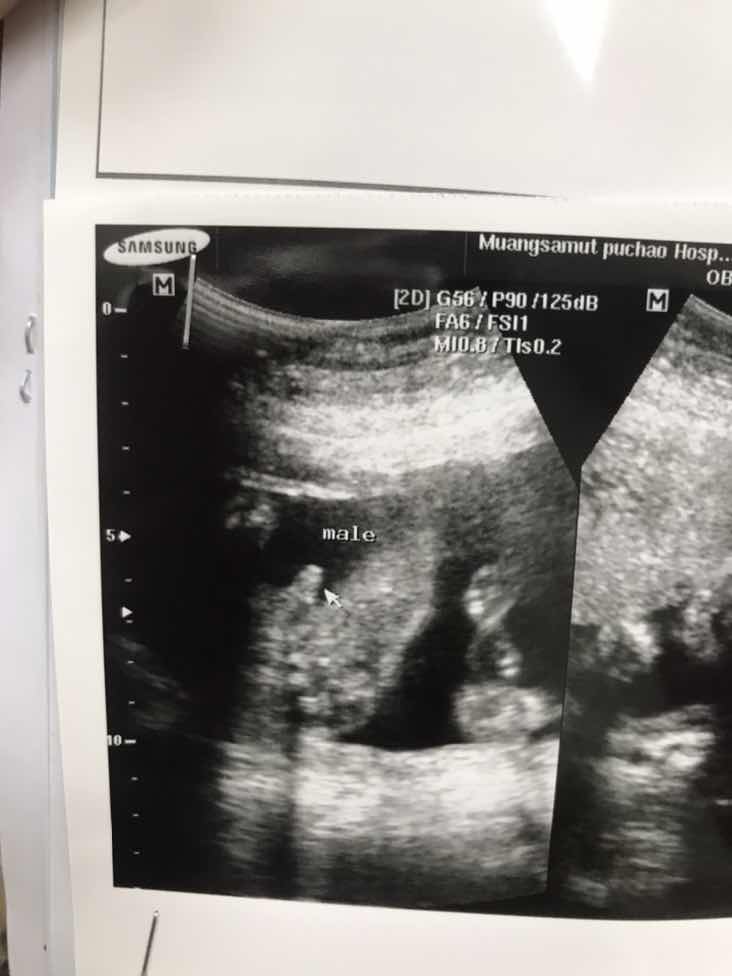

ใบอัลตร้าซาวด์

แม่ๆช่วยดูหน่อยคะ ผช.ใช่ไหมคะ หมอบอก ผช. บ้านไหนได้ ผช. ลงรูปใบซาวด์ให้ดูหน่อยคะ

ชายค่ะ

ผช. ค่ะ

ผ.ช ค่ะ

ผช. จ้า

ผช ค่ะ

ผช.จ้า

ผช.ค่ะ

ผชจ้า

ผช.คะ